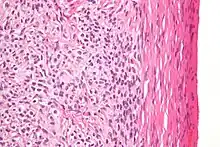

| High magnification micrograph of a thecoma. H&E stain. | |

Low magnification micrograph of a thecoma showing compression of the ovarian cortex (right of image). H&E stain.

Microscopically, the tumour cells have abundant lipid-filled cytoplasm.